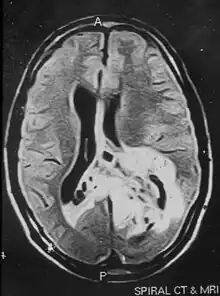

Non-contrast magnetic resonance imaging showing hyper-intense lesion involving the left temporal and parieto-occipital regions. The tumor is crossing the midline to the right parietal region.

An MRI image of a brain tumor occupying the left temporal and parieto-occipital regions of the brain.